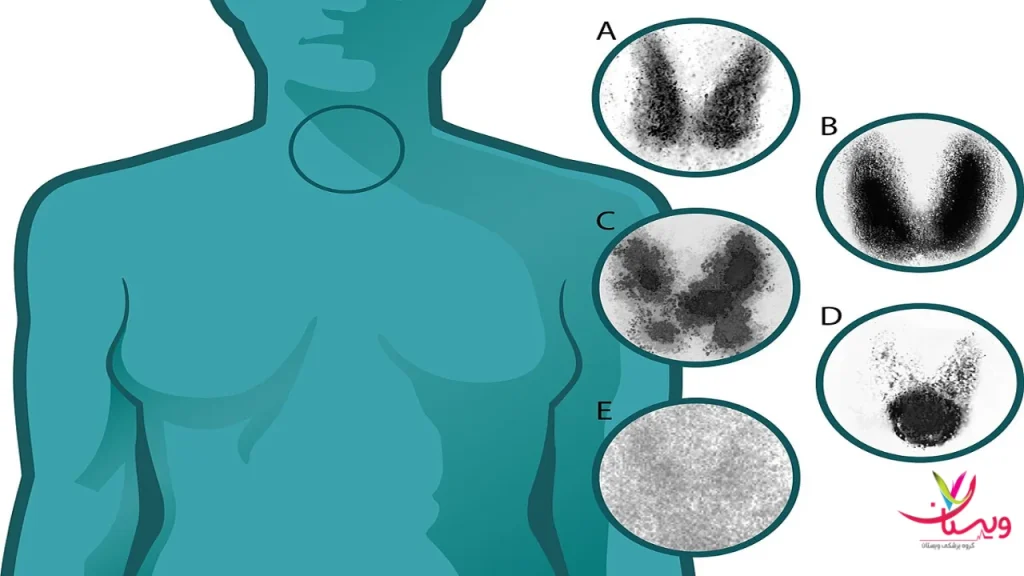

ندولهای تیروئید: گرم، سرد یا ایزو

یکی از مهمترین کاربردهای اسکن هستهای تیروئید بررسی ندولها یا تودههای تیروئیدی است.

- ندول گرم: ناحیهای که فعالیت بالایی دارد و معمولاً خوشخیم است.

- ندول سرد: فعالیت کمی نشان میدهد و در مواردی نیاز به بررسی بیشتر از طریق سونوگرافی یا نمونهبرداری دارد.

- ندول ایزو: عملکرد طبیعی دارد و اغلب نگرانکننده نیست.

۲. نقشه اسکن: مناطق داغ و سرد

در اسکن هستهای تیروئید، تصاویر بهصورت نقشههایی از غده تیروئید ارائه میشود که در آن نواحی مختلف با رنگهای متفاوت نمایش داده میشوند:

- مناطق داغ (Hot Spots): این نواحی جذب بالای رادیودارو را نشان میدهند و معمولاً نشاندهنده فعالیت بالای غده در آن ناحیه هستند.

- مناطق سرد (Cold Spots): این نواحی جذب کمتری دارند و ممکن است نشاندهنده کاهش فعالیت یا وجود تودههای غیرطبیعی در آن ناحیه باشند.

توجه به این نواحی میتواند به تشخیص دقیقتر مشکلات تیروئید کمک کند.